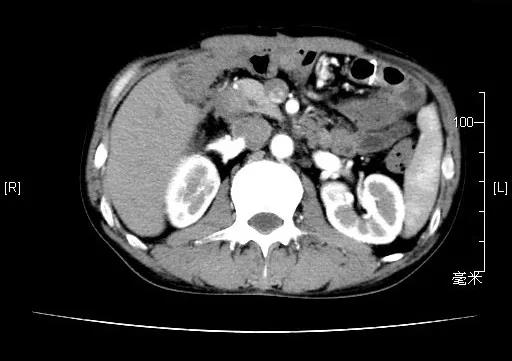

2020.05.26腹部CT(化疗3周期后)

2020.07.18腹部CT(化疗6周期后)